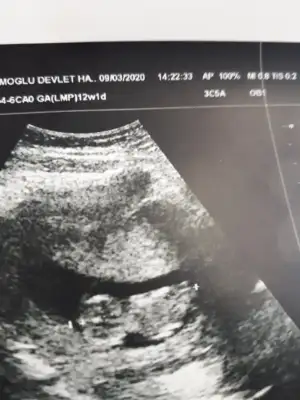

Kız sanki emin olamadım başka usgde paylaşınKızlar tahminde bulunabilirmisiniz ikiz bebekler 12 hafta 1 gunlikler

Bu kadar usg görüntüleri var malesefKız sanki emin olamadım başka usgde paylaşınsagdaki kız gibi digeri hiç görünmüyor

Tek yumurta ikizimi sanki ikiside kız tekrar usg olursa paylaşırsınız 13 haftada olurBu kadar usg görüntüleri var malesef![]()